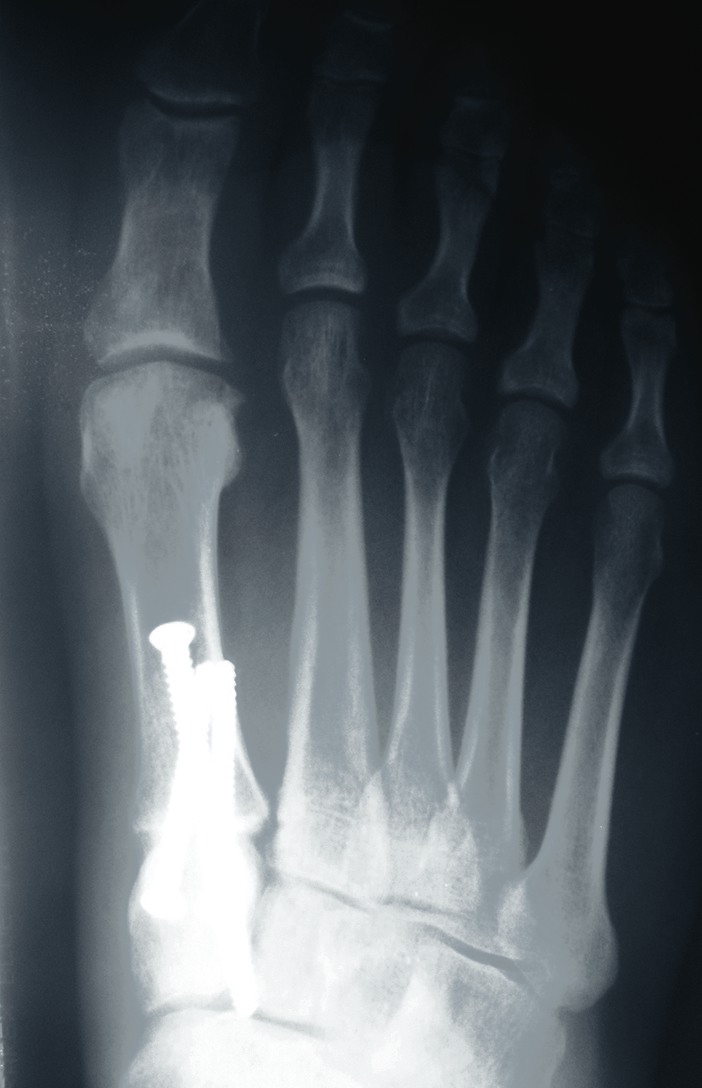

One should place the patient into a supine position and utilize a tourniquet. Evaluate post-anesthesia assessment of the first MPJ range of motion. Manually distract the first MPJ and plantarflex the first metatarsal. Dorsiflex the hallux to determine the obtainable first MPJ range of motion and evaluate for crepitus. If there is first ray hypermobility and no crepitus, one may be able to salvage the first MPJ by translating the first ray plantarly and stabilizing the medial column. Initially, surgeons should address contributing global pathology. Then proceed to the first ray and make a dorsomedial skin incision spanning the first MPJ. Retract the neurovascular structures. Make a longitudinal incision to bone, spanning the distal one-third of the first metatarsal and proximal one-half of the proximal phalanx. Evaluate the adjacent cartilage and make a critical decision to preserve or destroy the joint. It is important to realize that evaluation of cartilage quantity and quality via direct intraoperative visualization weighs heavily upon the final decision to perform a joint preservation or destructive procedure. One should strongly consider joint destructive procedures if greater than 30 percent of the dorsal portion of the first metatarsal head presents as grade III to grade IV chrondromalacia. One must independently evaluate grade III and IV chrondromalacia and osteochondral defects in the remaining 70 percent of the metatarsal head. Small cartilage lesions may yield themselves to debridement, drilling or OATS procedures whereas large cartilage defects will likely result in arthrodesis. If the joint is salvageable and one identifies first metatarsocuneiform hypermobility, perform a cheilectomy and a subsequent, sagittal Lapidus procedure. If one identifies hypermobility or posttraumatic first metatarsal angular pathology, correct it after completing the first MPJ soft tissue and osteophyte debridement. If one decides to perform arthrodesis on the joint, debride identified osteophytes, loose bodies, synovitis and scar tissue. Denude the adjacent cartilaginous surfaces to the healthy level of bleeding bone via curettage or via convex distal and concave proximal reamers. Fenestrate the adjacent bone surfaces with a 1.0- or 1.5-mm drill bit. Temporarily fixate the hallux by utilizing two K-wires in the desired position. The position should be approximately 20 to 30 degrees dorsiflexed in relation to the first metatarsal declination; abducted and parallel to the second digit; and with the nail void of frontal plane varus or valgus rotation. Obtain an AP radiograph to evaluate the bony apposition and alignment of the proposed first MPJ arthrodesis. Also obtain a lateral radiograph with the foot loaded in order to evaluate the hallux and its relationship to the first ray. After obtaining the desired position, utilize two fully threaded (3.5 or 4.0) crossing cortical screws for permanent fixation. Place the first screw from proximal medial to distal lateral and place the second screw from distal medial to proximal lateral across the first MPJ. Ensure the screws do not cross at the level of the joint. Use a 3.5-mm burr to create a dell in the cortical bone where the head of the screws engage the bone as Manloli and Hansen have described.48 After obtaining rigid internal fixation across the first MPJ, utilize a shear strain autograft (harvested via a percutaneous calcaneal grafting technique) at the arthrodesis site.57 Place the autograft in two troughs created by the 3.5-mm burr at the arthrodesis site. Use a bone mallet and tamp to provide a press fit.58